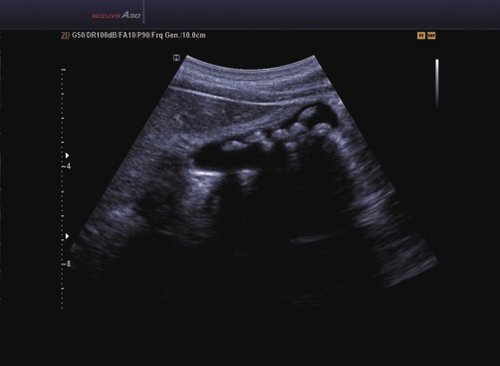

Das Samsung Accuvix A30 ist ein hochwertiges Ultraschallsystem, das mit seiner 3D-Technologie herausragende Ergebnisse ermöglicht. Das Sonographiegerät besitzt 5 Sondenanschlüsse und ist mit 20 unterschiedlichen Schallköpfen kompatibel. Mit dem A30 können Schallköpfe vom Typ Konvex, Mikrokonvex, 3D-Konvex, CW, Phased Array, Linear und Endokavitär verwendet werden. Bei zwei der Sonden handelt es sich um S-VUE Ultraschallsonden, die durch ihre höhere Bandbreite noch feinere Scans erzeugen.

Das Ultraschallsystem hebt sich besonders durch seine 3D-Technologie wie die Face Auto Detection für detaillierte Ultraschallbilder von Föten oder das Volume Shade Imaging, das sich auf die lebensnahe Darstellung von Schattierungen und Hauttönen fokussiert, ab. Mit weiteren wertvollen Technologien wie dem ElastoScan™ werden Tumore schneller erfasst und durch die HD Volumen Bildgebung sowie das DMR+™ eine erstklassige Bildqualität erzielt.

• FAD™, die Face Auto Detection, stellt das Gesicht eines Fötus besonders detailliert dar. Überflüssige Daten werden entfernt und ein besonders realistisches Bild gezeichnet.

• Volume Shade Imaging, kurz VSI™, visualisiert ein 3D-Bild, das Hauttöne und Schattierungen auf ein qualitativ neues Niveau hebt.